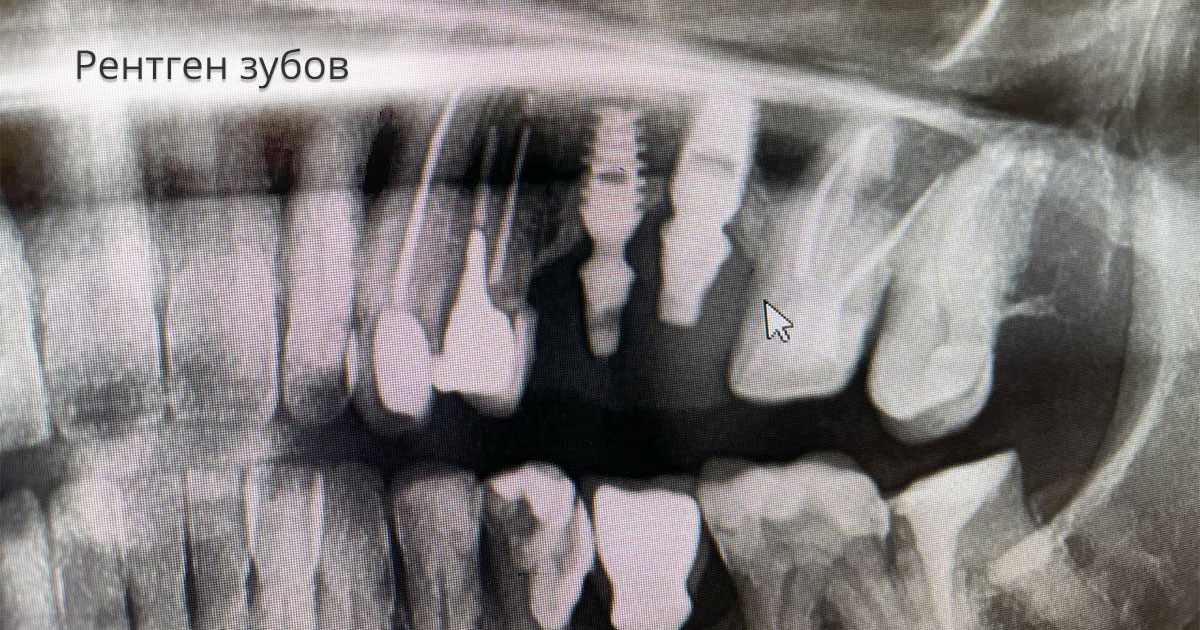

Рентгеновские снимки посттравматического остеомиелита челюсти: Медицинские случаи

Раздел: Образы вокруг